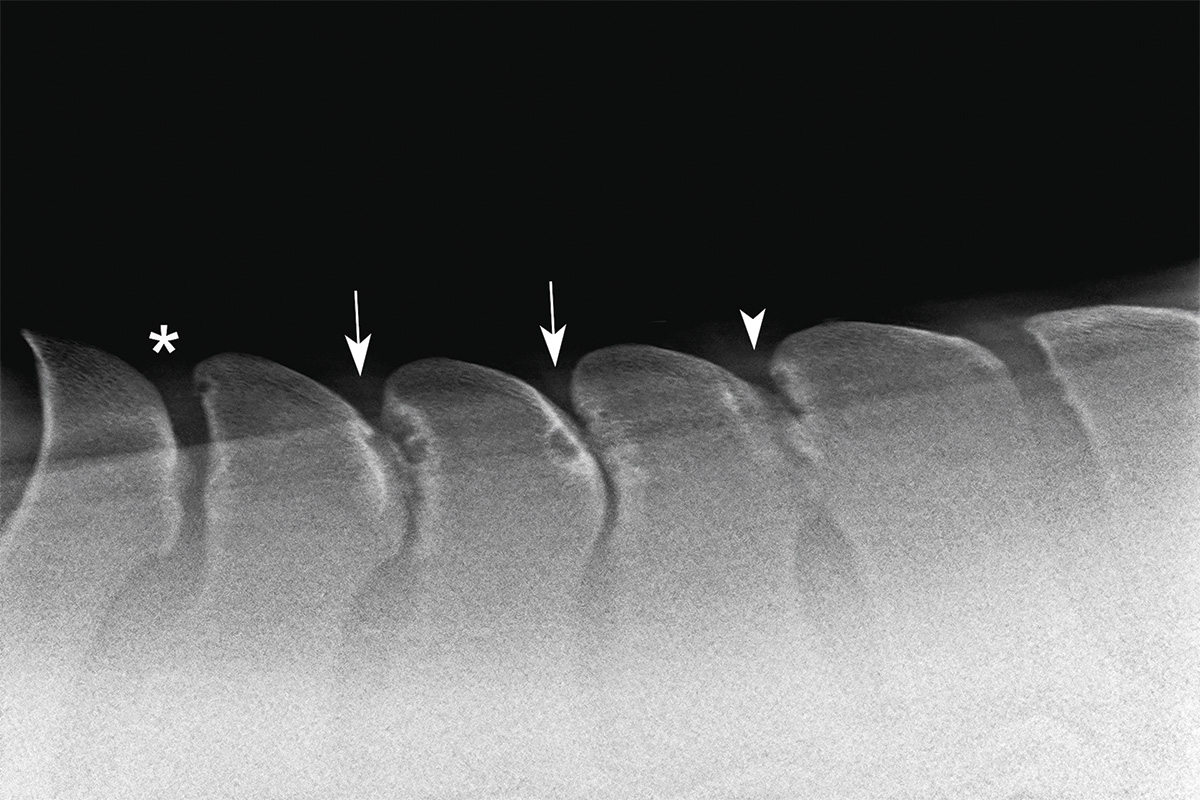

El término kissing spines se refiere a una patología denominada médicamente procesos espinosos dorsales sobrepuestos(Overriding Dorsal Spinous Processes, ORDSP).

Se produce cuando las apófisis espinosas de las vértebras dorsales (habitualmente entre la T13 y la T18) se aproximan demasiado o llegan a tocarse.

En los casos más severos, incluso rozan entre sí, provocando inflamación, dolor y contractura muscular.

Las radiografías son fundamentales para confirmar el diagnóstico, pero no siempre cuentan toda la historia.

Algunos caballos con imágenes muy marcadas no muestran síntomas, mientras que otros con hallazgos leves sí presentan molestias severas.